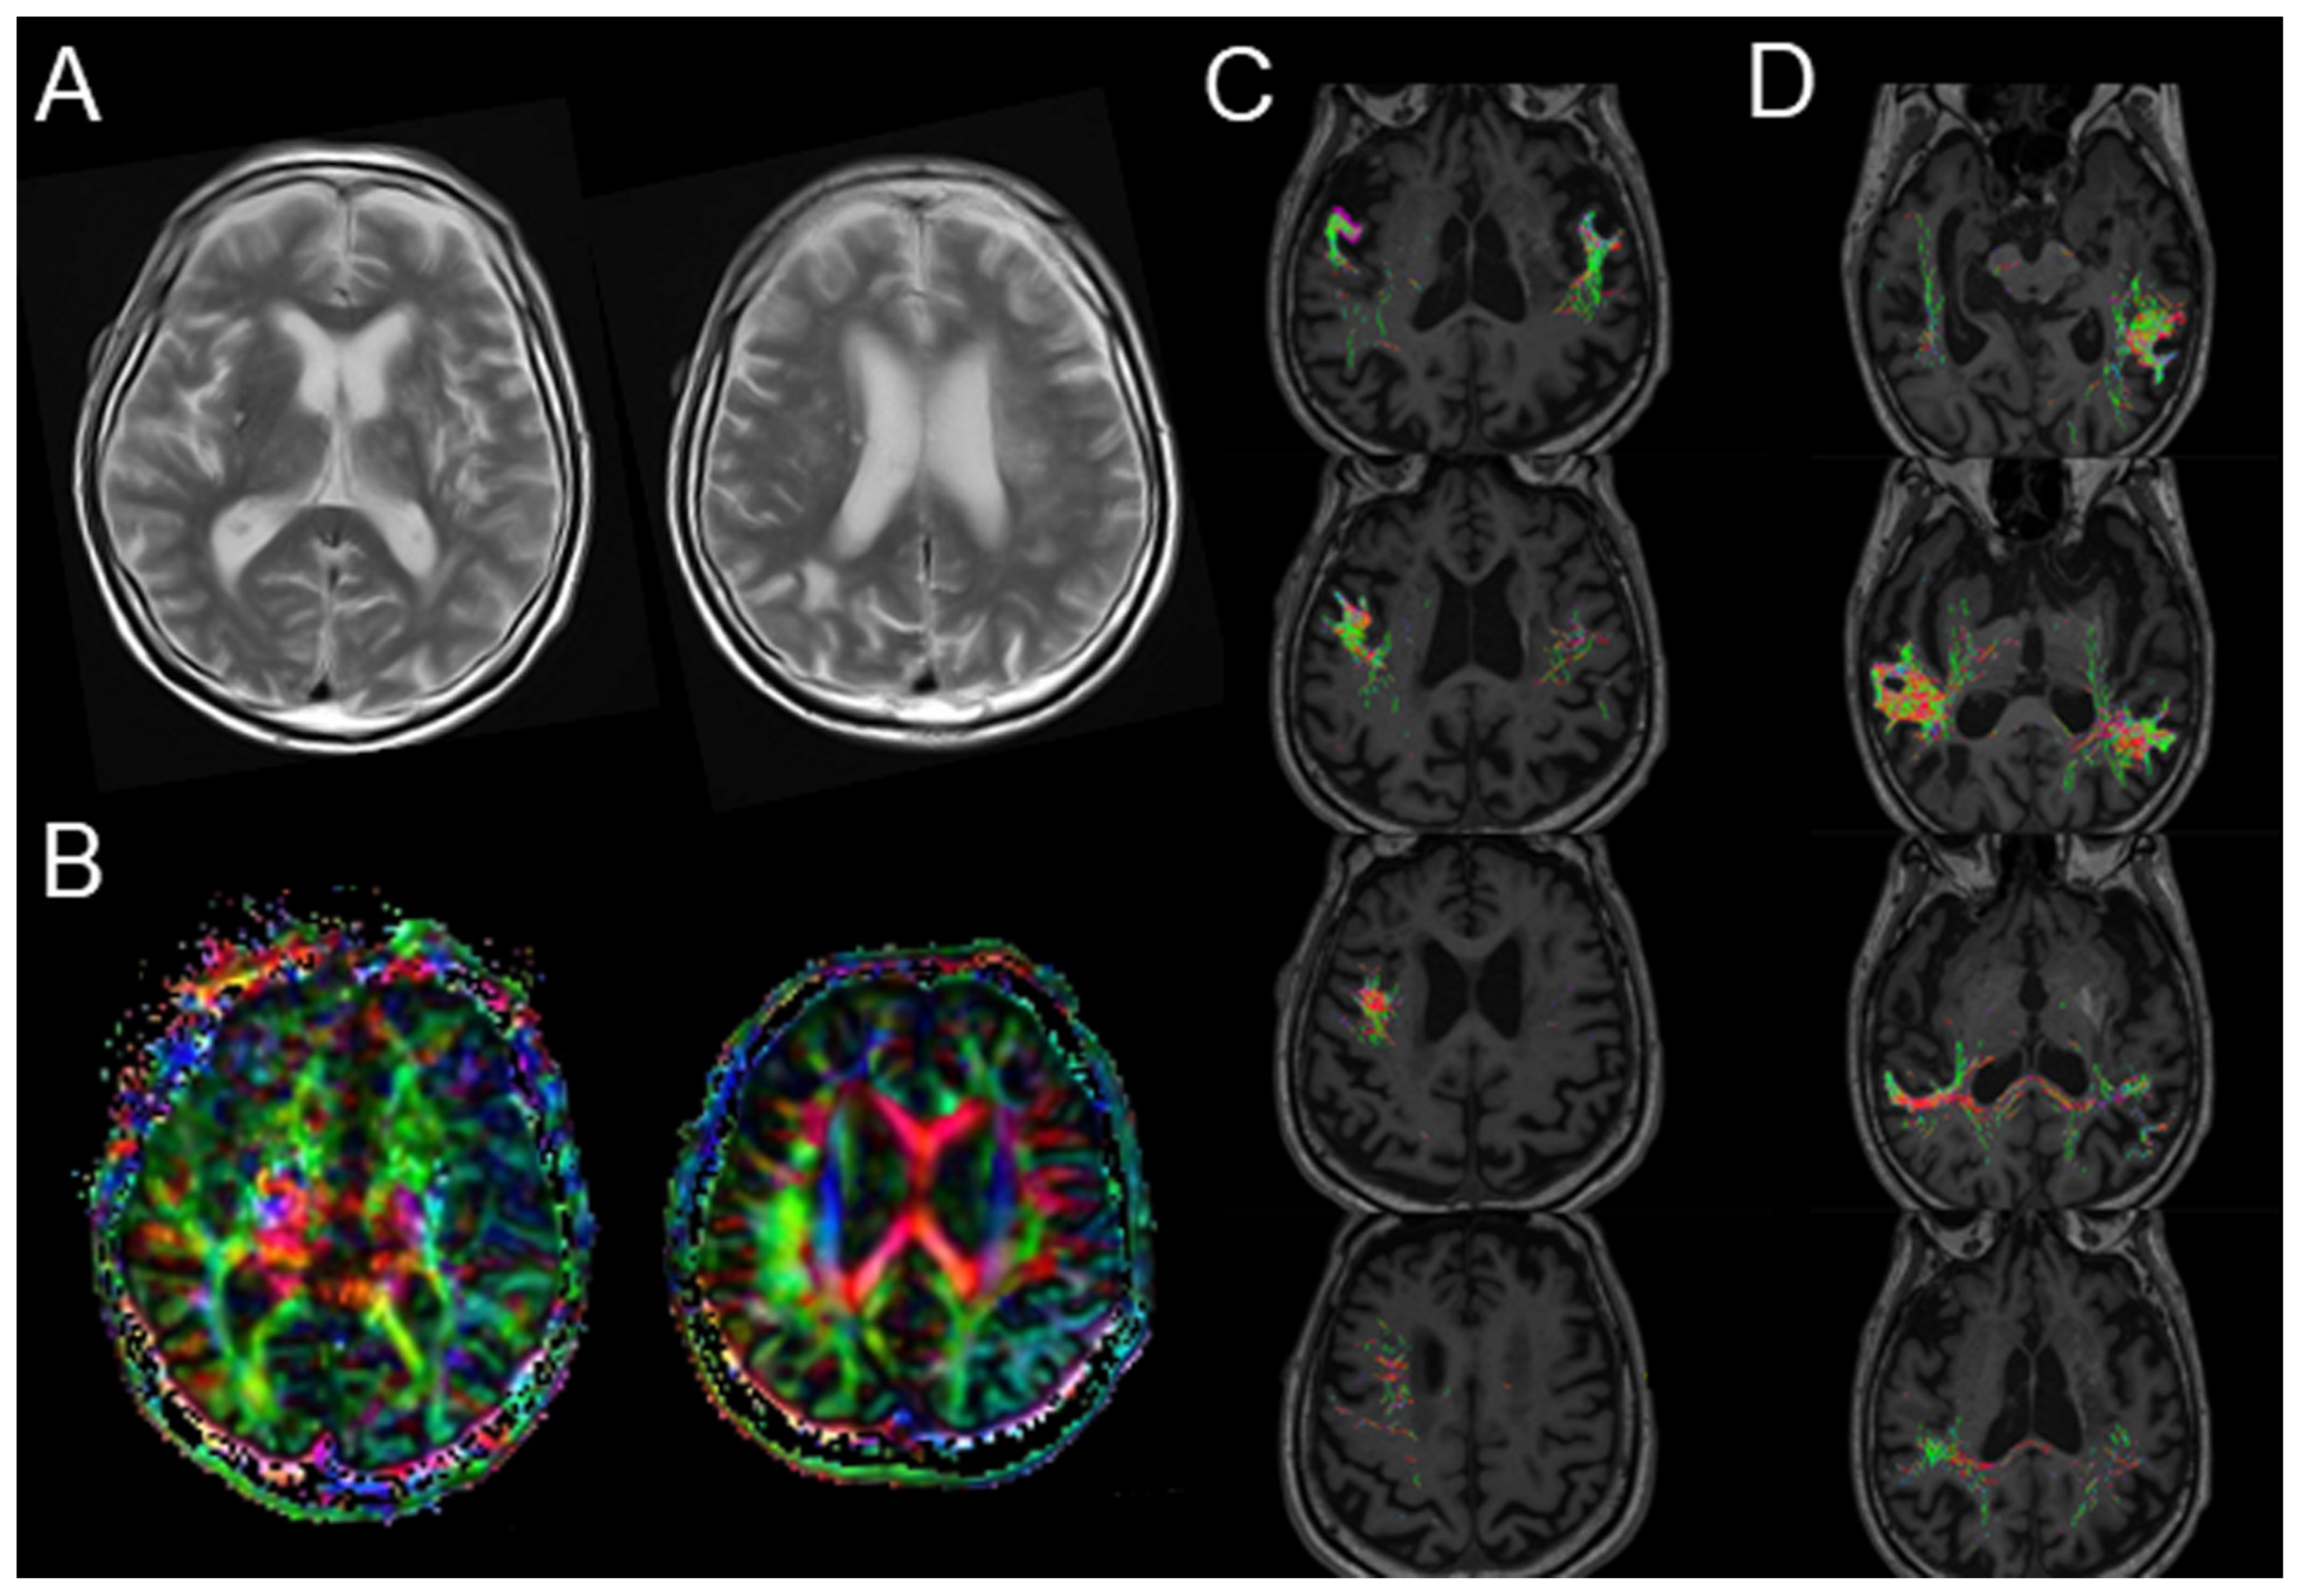

Diffusion MRI Fiber Tractography and Benzodiazepine SPECT Imaging for Assessing Neural Damage to the Language Centers in an Elderly Patient after Successful Reperfusion Therapy

2. Case Presentation